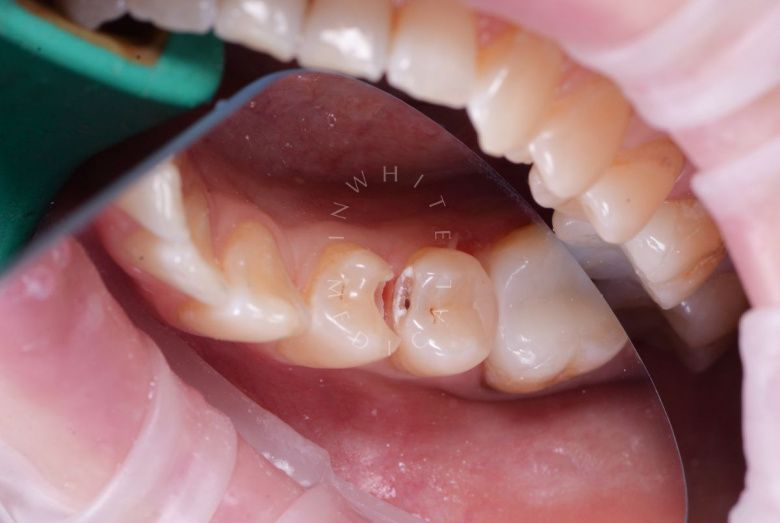

Лечение фиссурного кариеса под увеличением

Стоматология Москва лучшие клиники. Лечение фиссурного кариеса под увеличением - до процедуры